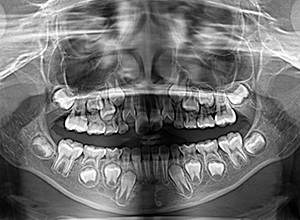

X-Ray

X-Ray所見

セファロ所見 下顎骨体部は大きく下顎枝は前傾しており下顎角は鈍角であった。上顎骨はやや劣位で奥行きがなく下顔面高は高くなっていた。

家族歴や側貌所見、下顎は大きいもののANBは2°でSellaに対して下顎頭は後方に位置していることなどから将来的に重度な下顎前突へ移行することは少ないと予測できた。

パノラマ所見 上顎アーチレングスディスクレパンシー(-)であるが、その他の異常所見は認められなかった。